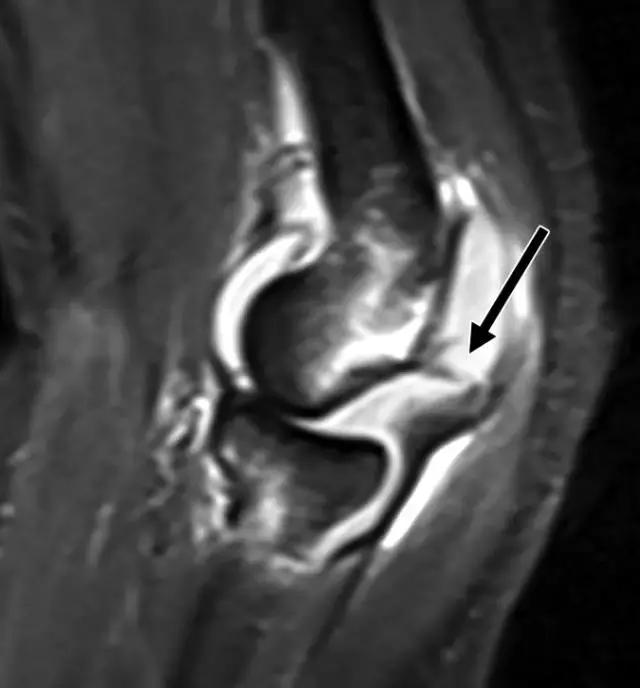

X线照片可能在髁间隙中显示小的骨折片段,或胫前胫骨关节面内的微小透亮区(图7A)。CT可能有助于确定撕裂片段的大小和粉碎程度,如果足够大可以允许螺钉固定片段,并避免ACL的重建。术前MRI也可能有助于评估ACL的外观和识别任何相关的半月板或韧带损伤(图7B)。

图7B,矢状质子密度加权的MR图像证实ACL嵌入部位的(箭头)撕裂性骨折(箭头)。